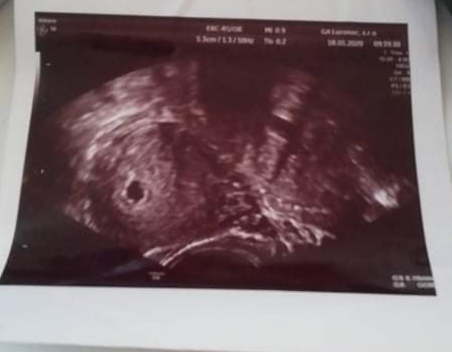

som tehotná, ale môj gynekológ mi nepovedal, v ktorom som týždni. Povedal iba veľkosť plodu 6,16 mm.

Podľa veľkosti plodu ide odhadom o 6 až 7 týždeň.